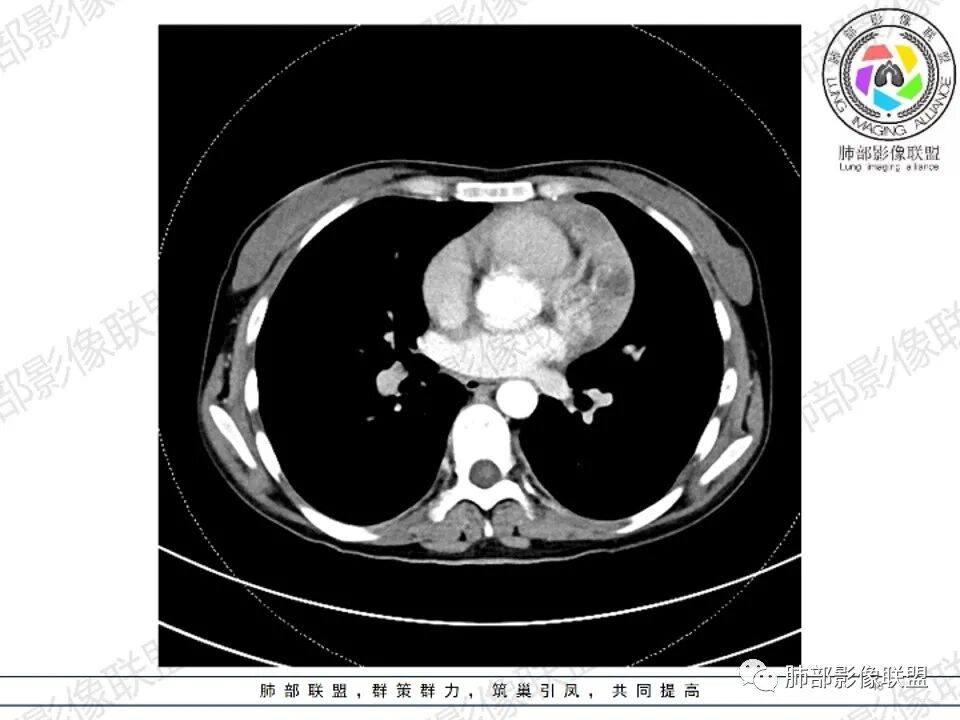

女,27,间断头晕、乏力3年,左眼视物模糊2月。贫血。胸部CT:前纵隔不规则肿块,多结节融合,边界不清,沿主动脉及肺动脉间隙生长,平扫密度欠均匀,增强扫描可见多发低密度坏死,纵隔血管供血穿行,腋窝多发大小不等淋巴结肿大。考虑恶性病变,胸腺癌?肉瘤?淋巴瘤?鉴别胸腺瘤、结节病等。

临床:年轻女性,慢性病程,多系统病变,头晕,贫血,视物模糊。

CT:定位纵膈病变,前中纵隔多发肿块,质软,塑形,密度不均匀,边界清楚。增强不均匀强化,坏死边界清楚,血管漂浮征。双侧腋下多组淋巴结肿大,明显异常强化。

考虑淋巴瘤可能。

2.影像显示前纵隔不规则块状影,依势贴附心脏大血管旁,密度不均,边界不甚清楚,有结节融合感。

3.病灶轻度不均匀强化,可见血管穿行,散在液性低密度区。

双肺门未见肿大淋巴结。

4.双侧腋窝区见增大淋巴结,边界清楚。